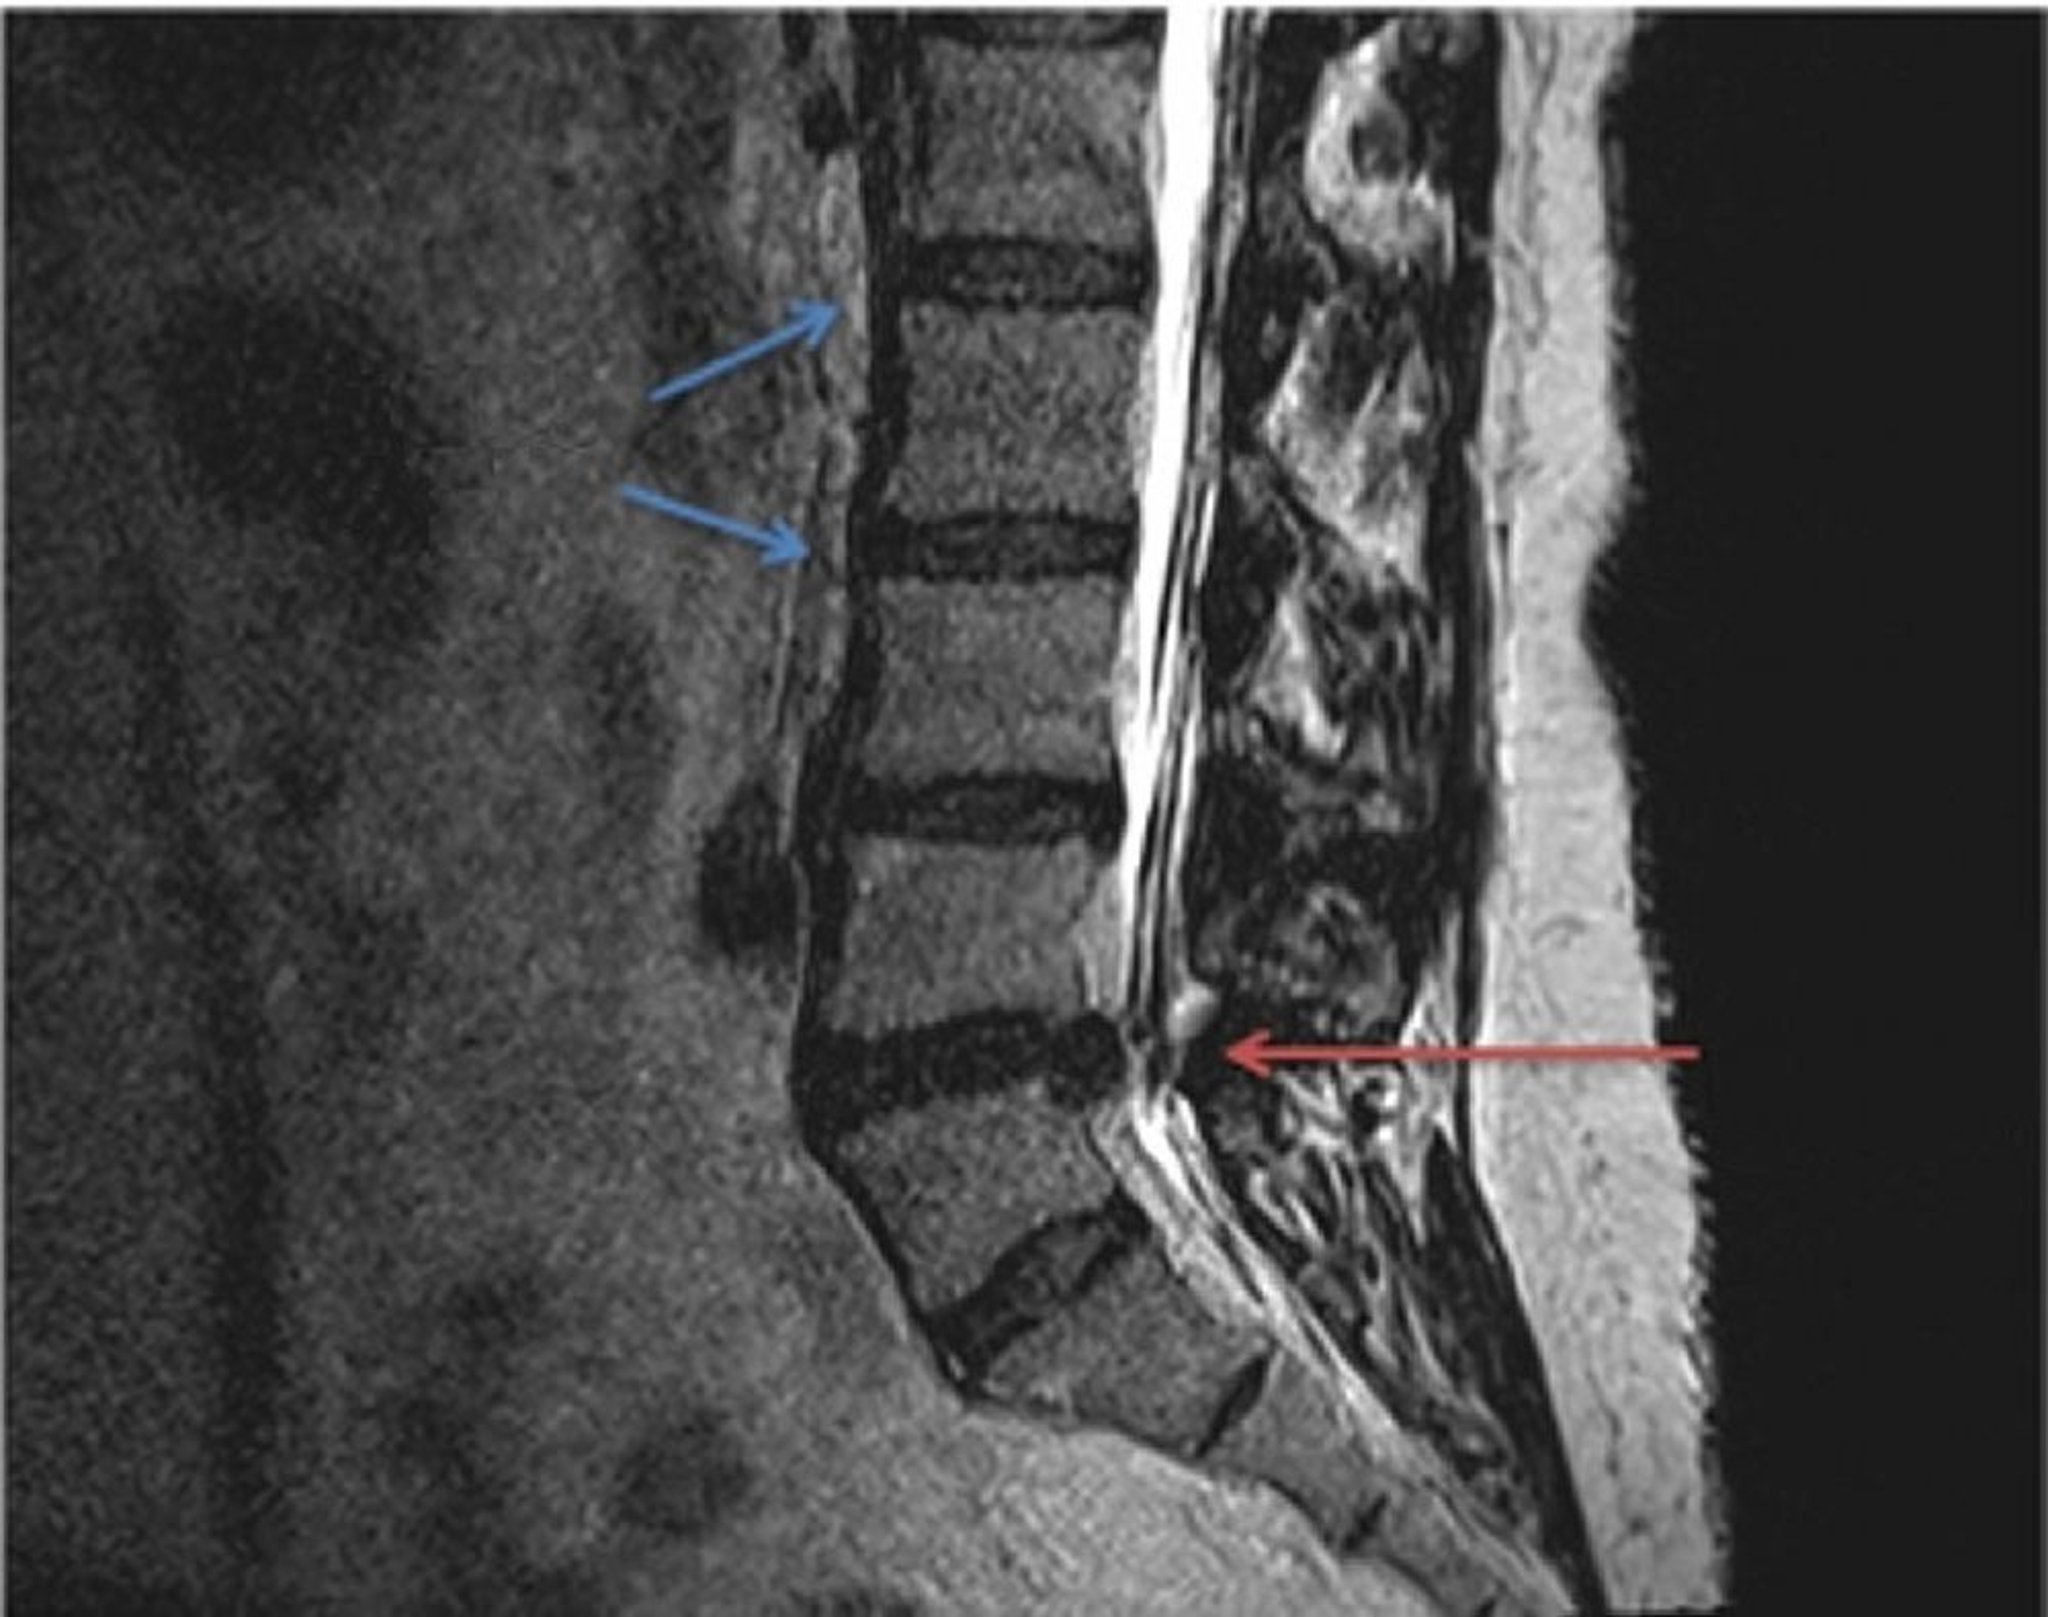

Thoát vị đĩa đệm (chụp MRI)

So sánh giải phẫu đĩa đệm thắt lưng bình thường (mũi tên màu xanh) và thoát vị trong chụp MRI có trọng số T2. Đĩa đệm thoát vị, nằm giữa đốt sống L4 và L5 (mũi tên đỏ), chèn ép dây thần kinh cột sống kéo dài từ tủy sống, gây ra áp lực và đau cục bộ hoặc đau lan tỏa.